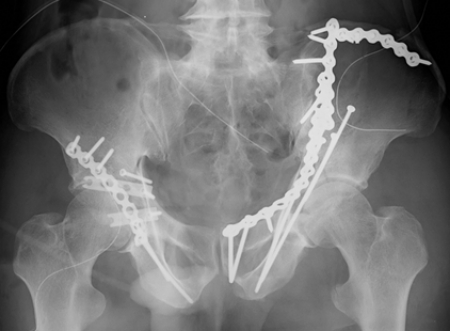

両側寛骨臼骨折 術後レントゲン

さらに当科の最大の特徴は整形外傷手術において最も難易度の高いうちの一つとされる骨盤・寛骨臼骨折治療を得意としているところであります。

現在年間50~60件の骨盤・寛骨臼骨折手術を当科で行っており、これは東海地区でもトップクラスであり、近隣の病院からも多くの手術目的の紹介をいただいております。

骨盤・寛骨臼骨折は受傷時に大量出血にて生命を脅かし得る損傷ですがこれに対しても迅速な血管塞栓術の対応が可能となっております。また近年こうした骨盤・寛骨臼骨折の患者様も高齢症例が増加しており内科的合併症が多い場合もございますがこれに対しても内科系救急医と協力し患者様に最善の治療を提供させていただいております。